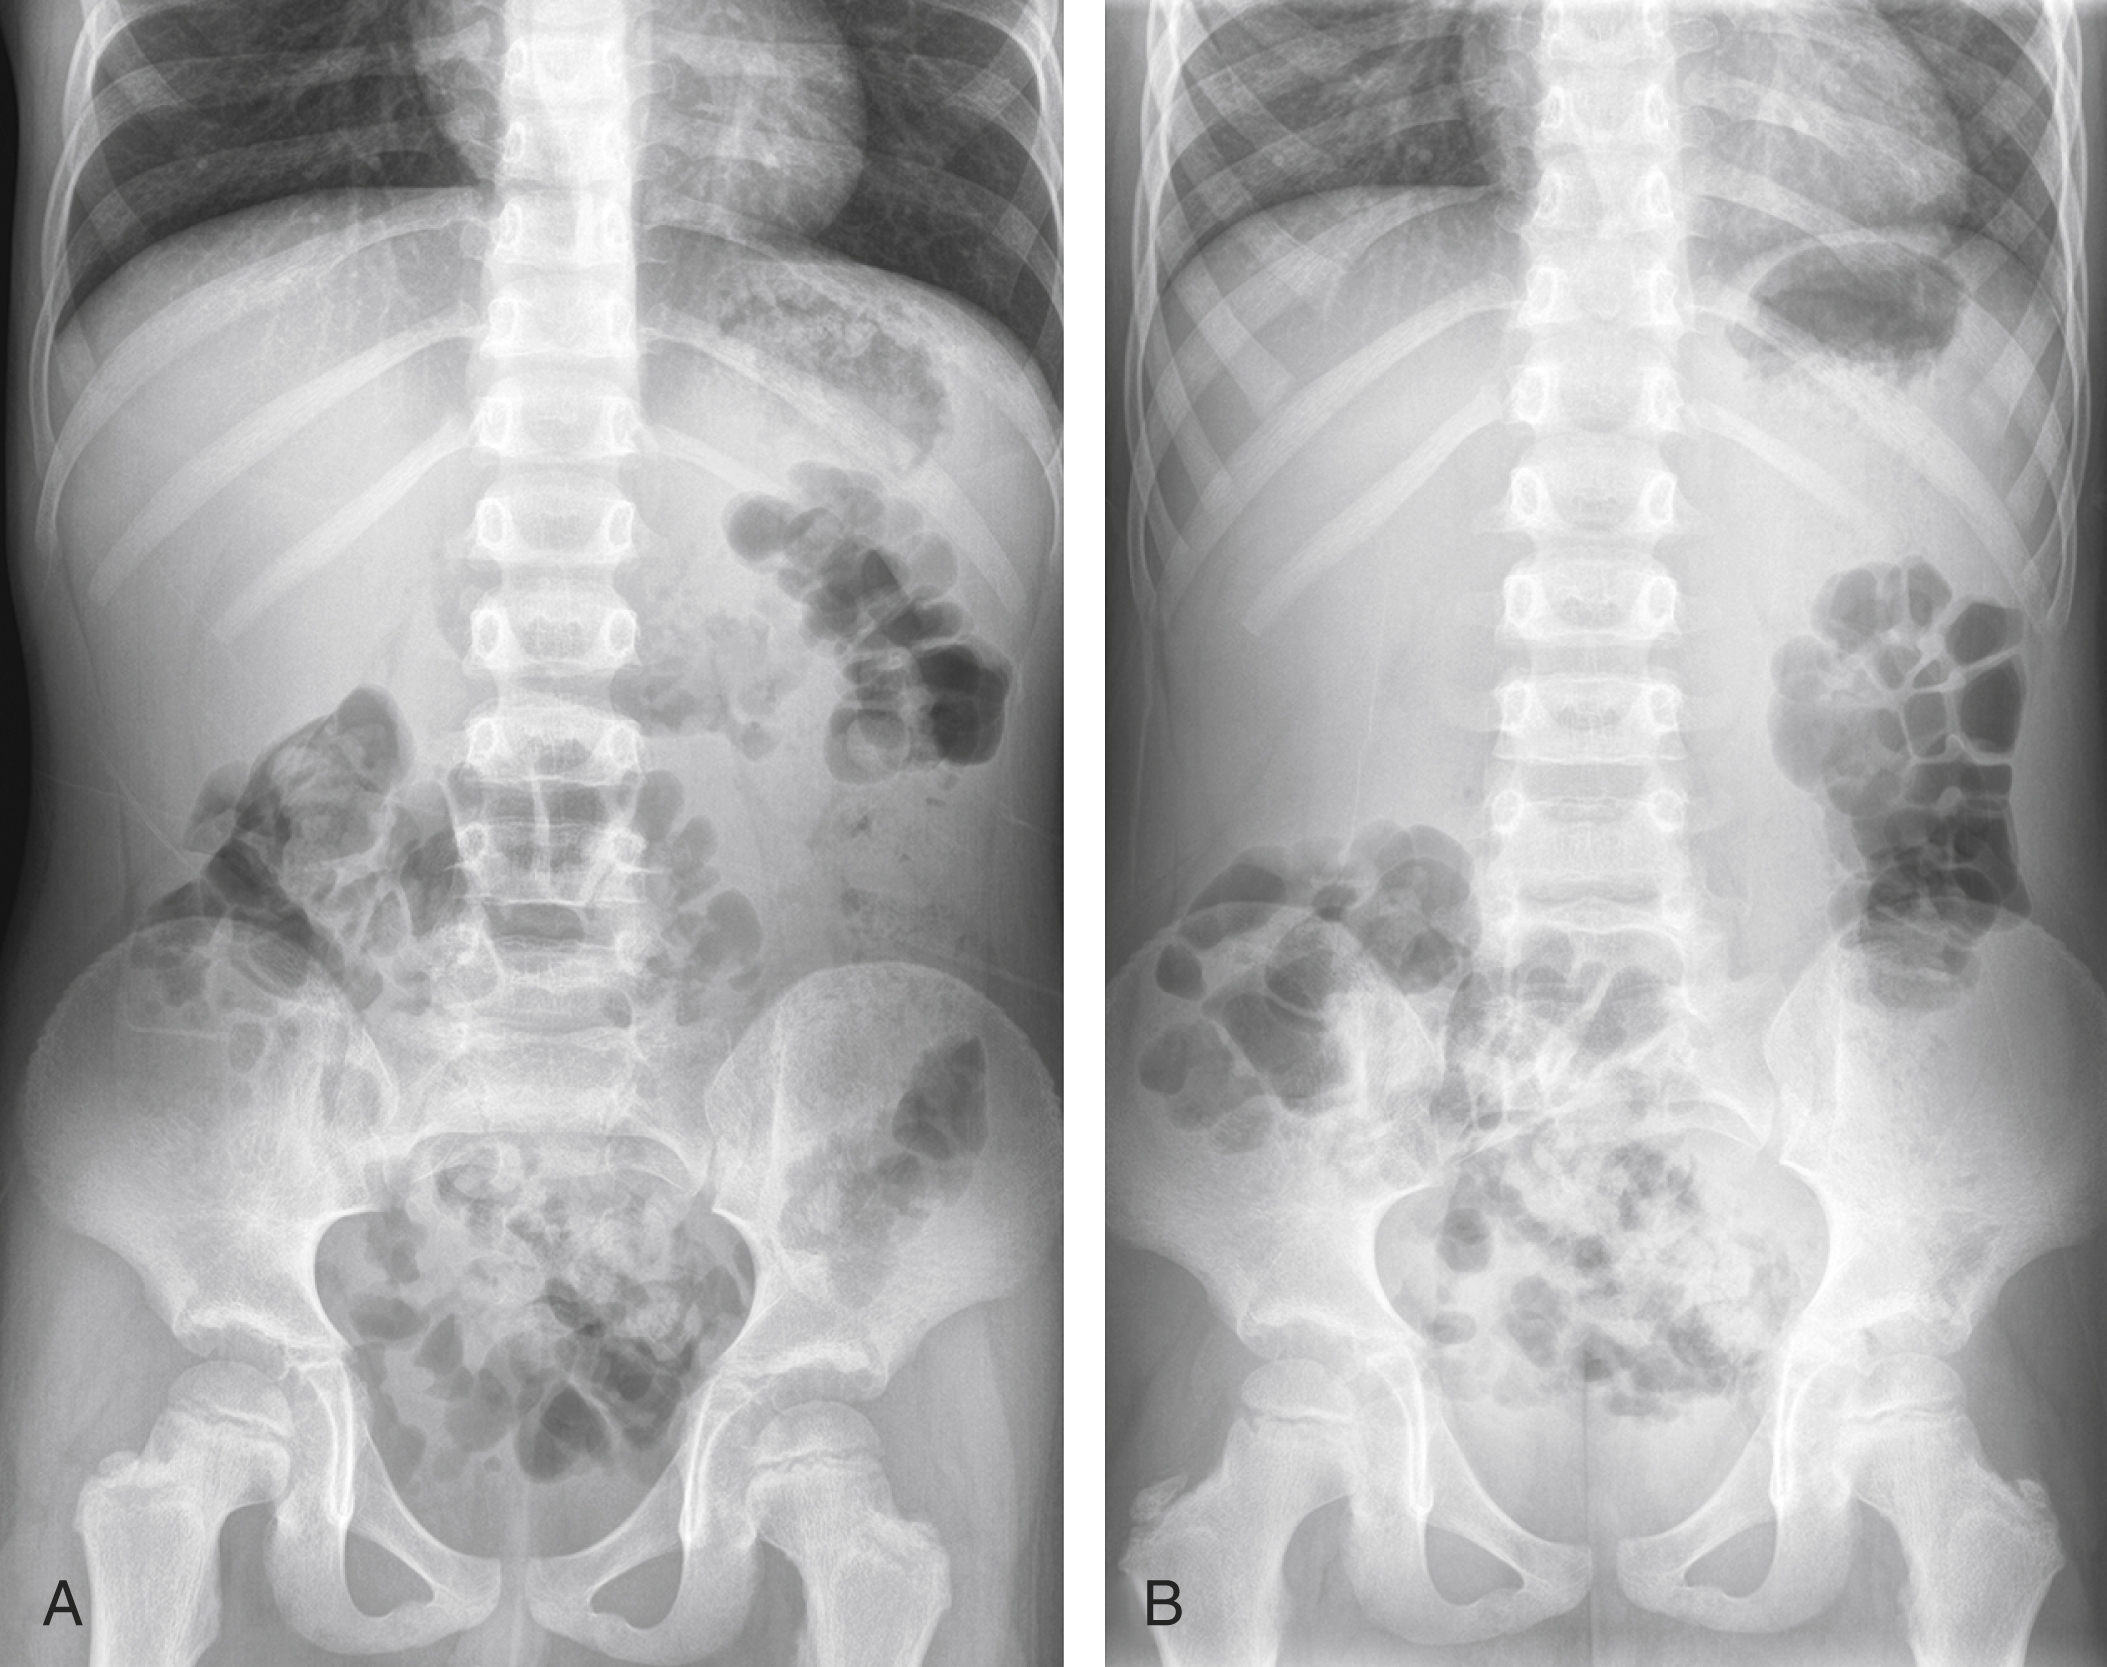

Pediatric Abdominal Pain Radiology Key